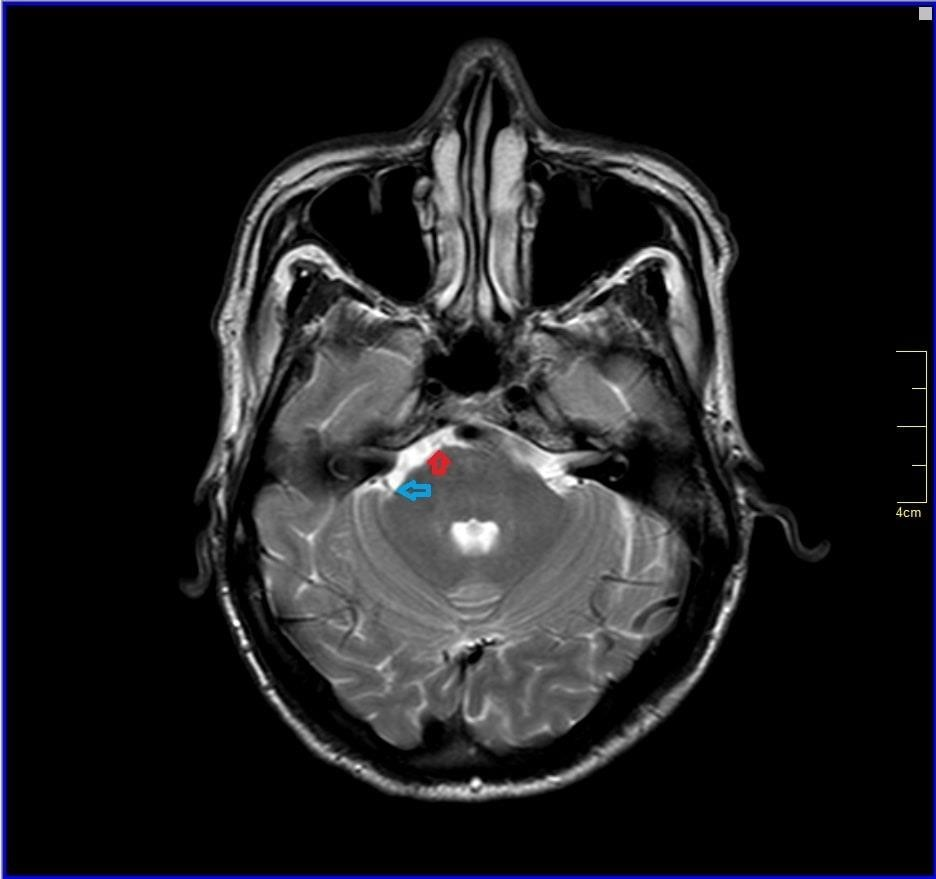

All other blood investigations including thyroid function tests and autoimmune screening were within normal limits. Plain computed tomography (CT) brain was done and revealed well-defined hypodensities seen in right lentiform nucleus chronic infarct.1 Otherwise, no intracranial haemorrhage and no acute ischemic infarcts seen at other areas. Brain magnetic resonance angiography (MRA) was ordered and it showed impingement of V4 vertebral artery to anterior lower pons near midline which is the exit of the left abducens nerve from the pons and also trigeminal nerve (blue arrow) and right abducens nerve (Figure 1-3) No abnormal signals were seen in brainstem. After ruling out other aetiologies of sixth cranial nerve, diagnosis of isolated sixth cranial nerve palsy was made.

Figure 2 Brain magnetic resonance angiography (MRA) showing impingement of V4 vertebral artery (red arrow) to anterior lower pons near midline which is the exit of the left abducens nerve from the pons.

Figure 3 Brain magnetic resonance angiography (MRA) showing trigeminal nerve (blue arrow) and right abducens nerve (red arrow).